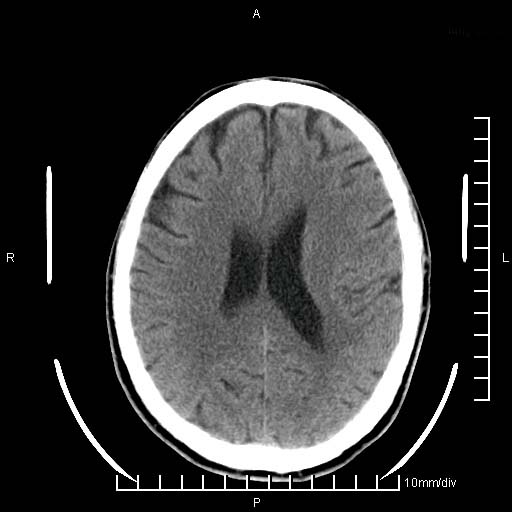

临床以双下肢浮肿,疼痛收治,无明显神经系统症状,既往无梗塞,出血病史。左颞叶见低密度灶,考虑什么?

考虑左侧颞叶脑软化灶。

无强化 无占位 软化灶吧

无强化、 无占位、局部脑沟增宽, 软化灶吧。